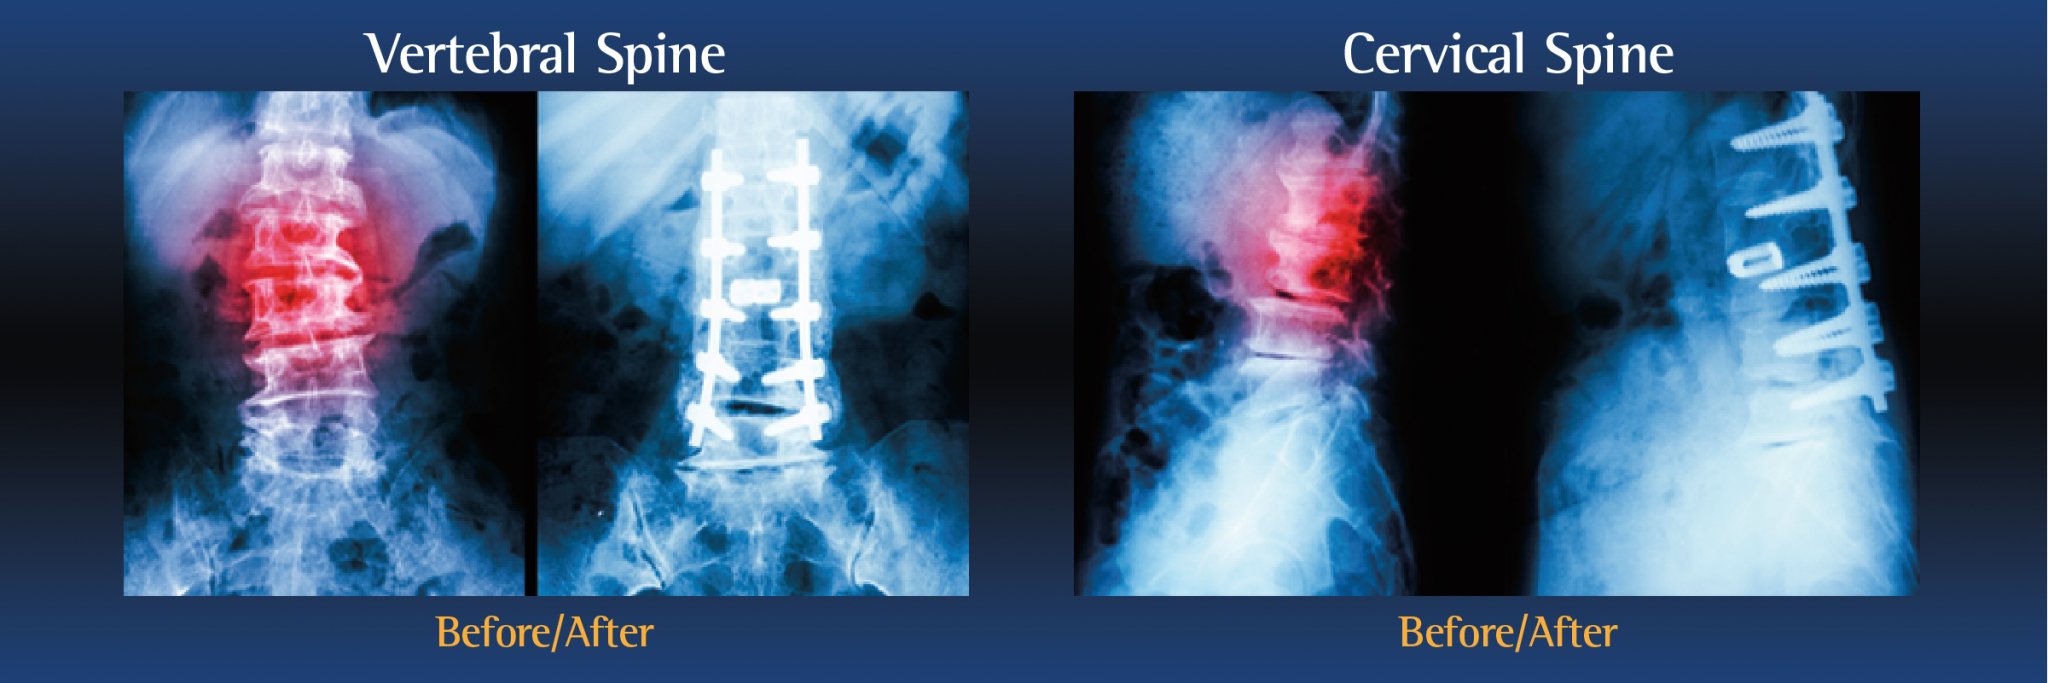

• Cervical Fusion is performed on the neck

During the operation, an incision is made in the neck, back or abdomen. Bone, debris, bone growths, lamina, and/or the damaged vertebral disc may be cleared from the spine, creating more space and relieving pressure on the spinal nerves. The surgeon will then take the proper steps to correct the patient’s specific problem.

Bone grafts may then be placed in the space or along the side of the spine. If additional support is needed, metal hardware (including pins or screws), may be used to steady the spine as it fuses. The incision is closed to finalize the surgery.

The grafts will grow into solid bone, fusing together the vertebrae. Patients may have to wear a back brace post-surgery, which will support your spine and keep the vertebrae from moving as the grafts fuse together.